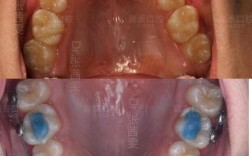

(图片来源网络,侵删)- 氯己定含漱液:广谱抗菌,能有效抑制口腔内细菌(如革兰氏阳性菌、阴性菌),减少继发感染,使用时需稀释(按说明书比例,通常用1:5稀释),每日3-5次,每次含漱30秒,避免长期使用(超过2周)可能导致舌苔染色、口腔黏膜脱屑。

(图片来源网络,侵删)- 阿莫西林:广谱青霉素类,对革兰氏阳性菌效果好,成人每次0.5g,每日3次,过敏者禁用。